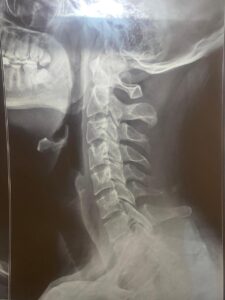

Advanced Spine Treatment for Slipped Disc, Nerve Compression & Disc Bulge

Specialized Treatment for Common Spine Conditions

Slipped Disc

Targeted therapy to reduce pressure and improve mobility.

Nerve Compression

Relieve nerve pressure and reduce radiating pain.

Disc Bulge